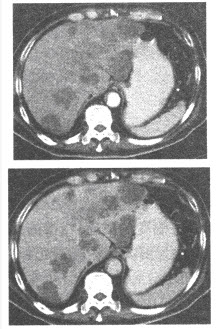

男,72岁,胆石症史多年。1个月来发热,上腹疼痛,CT扫描如下图,显示肝脏内多个直径10~30mm低密度灶,CT值20HU,边缘呈环状强化,最有可能的诊断是()

A:多发性囊状肝转移瘤

B:胆源性肝脓肿

C:多发性肝囊肿

D:肝包虫病

E:肝脏囊腺瘤